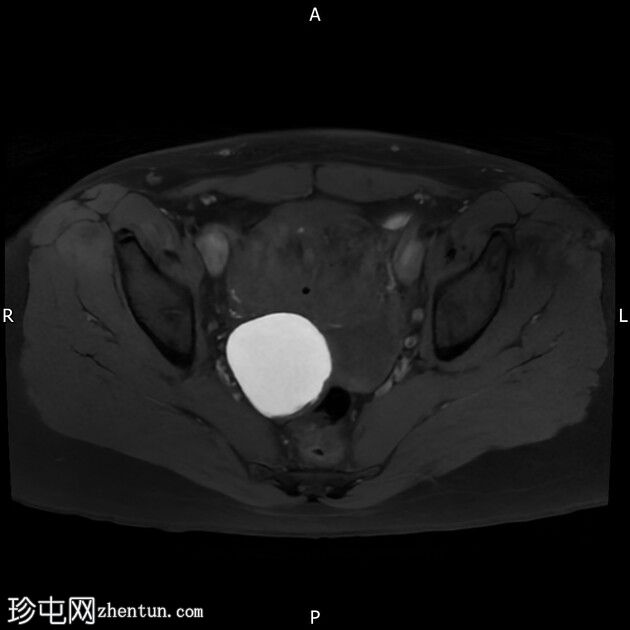

轴位T1加权像

增强脂肪抑制像

右侧卵巢囊肿,T2加权像呈低信号,T1脂肪抑制像呈高信号,大小为6 x 5.2 cm,符合子宫内膜异位囊肿的影像学表现。

左侧卵巢囊肿,T2加权像呈低信号,T1脂肪抑制像呈高信号,符合子宫内膜异位囊肿的影像学表现。

结论:双侧卵巢子宫内膜异位囊肿。多发性子宫肌瘤。

本病例显示右侧卵巢子宫内膜异位症,左侧卵巢囊肿内含出血性物质,并可见“接吻卵巢征”,诊断为卵巢子宫内膜异位囊肿伴可能粘连/深部盆腔子宫内膜异位症。

此外,还存在子宫肌瘤。